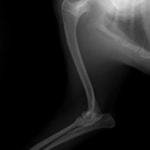

症例:トイプードル 9カ月齢

3ヵ月前より左前肢の跛行が認められるとのことで、来院されました。整形外科学的検査において、患肢の肘関節・肩関節重度の伸展制限が認められました。Xray検査において、左肩関節の内方脱臼、および肩甲骨関節窩の低形成と上腕骨頭の変形が認められました。

数か月に及ぶ慢性脱臼のため、関節面の低形成・摩耗のため整復手術による適切な再建は困難と判断し、切除関節形成術を実施しました。

術後3週間頃より、負重状態、歩行が改善しました。

切除関節形成術は、疼痛を引き起こす関節面を除去し、線維性偽関節の形成により患肢の機能改善を促す救済的手術です。術後のリハビリテーションの実施により、関節の可動域や患肢の筋肉量は改善され、生活の質は向上します。また本症例のように、慢性脱臼だけでなく、重度の骨関節炎症例にも実施することがあります。